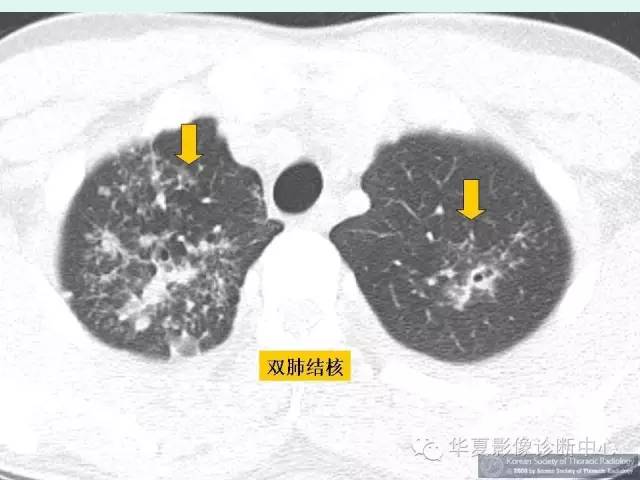

肺转移瘤的十种不典型CT表现